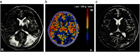

1. 高血圧性脳症は高血圧緊急症のひとつに含まれ、本来脳血管自動調節能(cerebral autoregulationを有する脳血管に閾値を超えた高血圧負荷がかかり、脳血管のvasospasmおよび血液脳関門BBBのbreak-through現象による血管原性浮腫を生じ、可逆的あるいは非可逆的な組織学的変化が起きる状態である。

1. 従来、このような病態はCTのみでは同定しにくいこともあったが、近年、MRI、MRA、脳灌流画像などにより、reversible cerebral vasoconstriction syndromeRCVSやPRESposterior reversible encephalopathy syndromeといったダイナミックな病態として捉えられるようになり、正しい診断が迅速な治療に結びつくようになってきた。